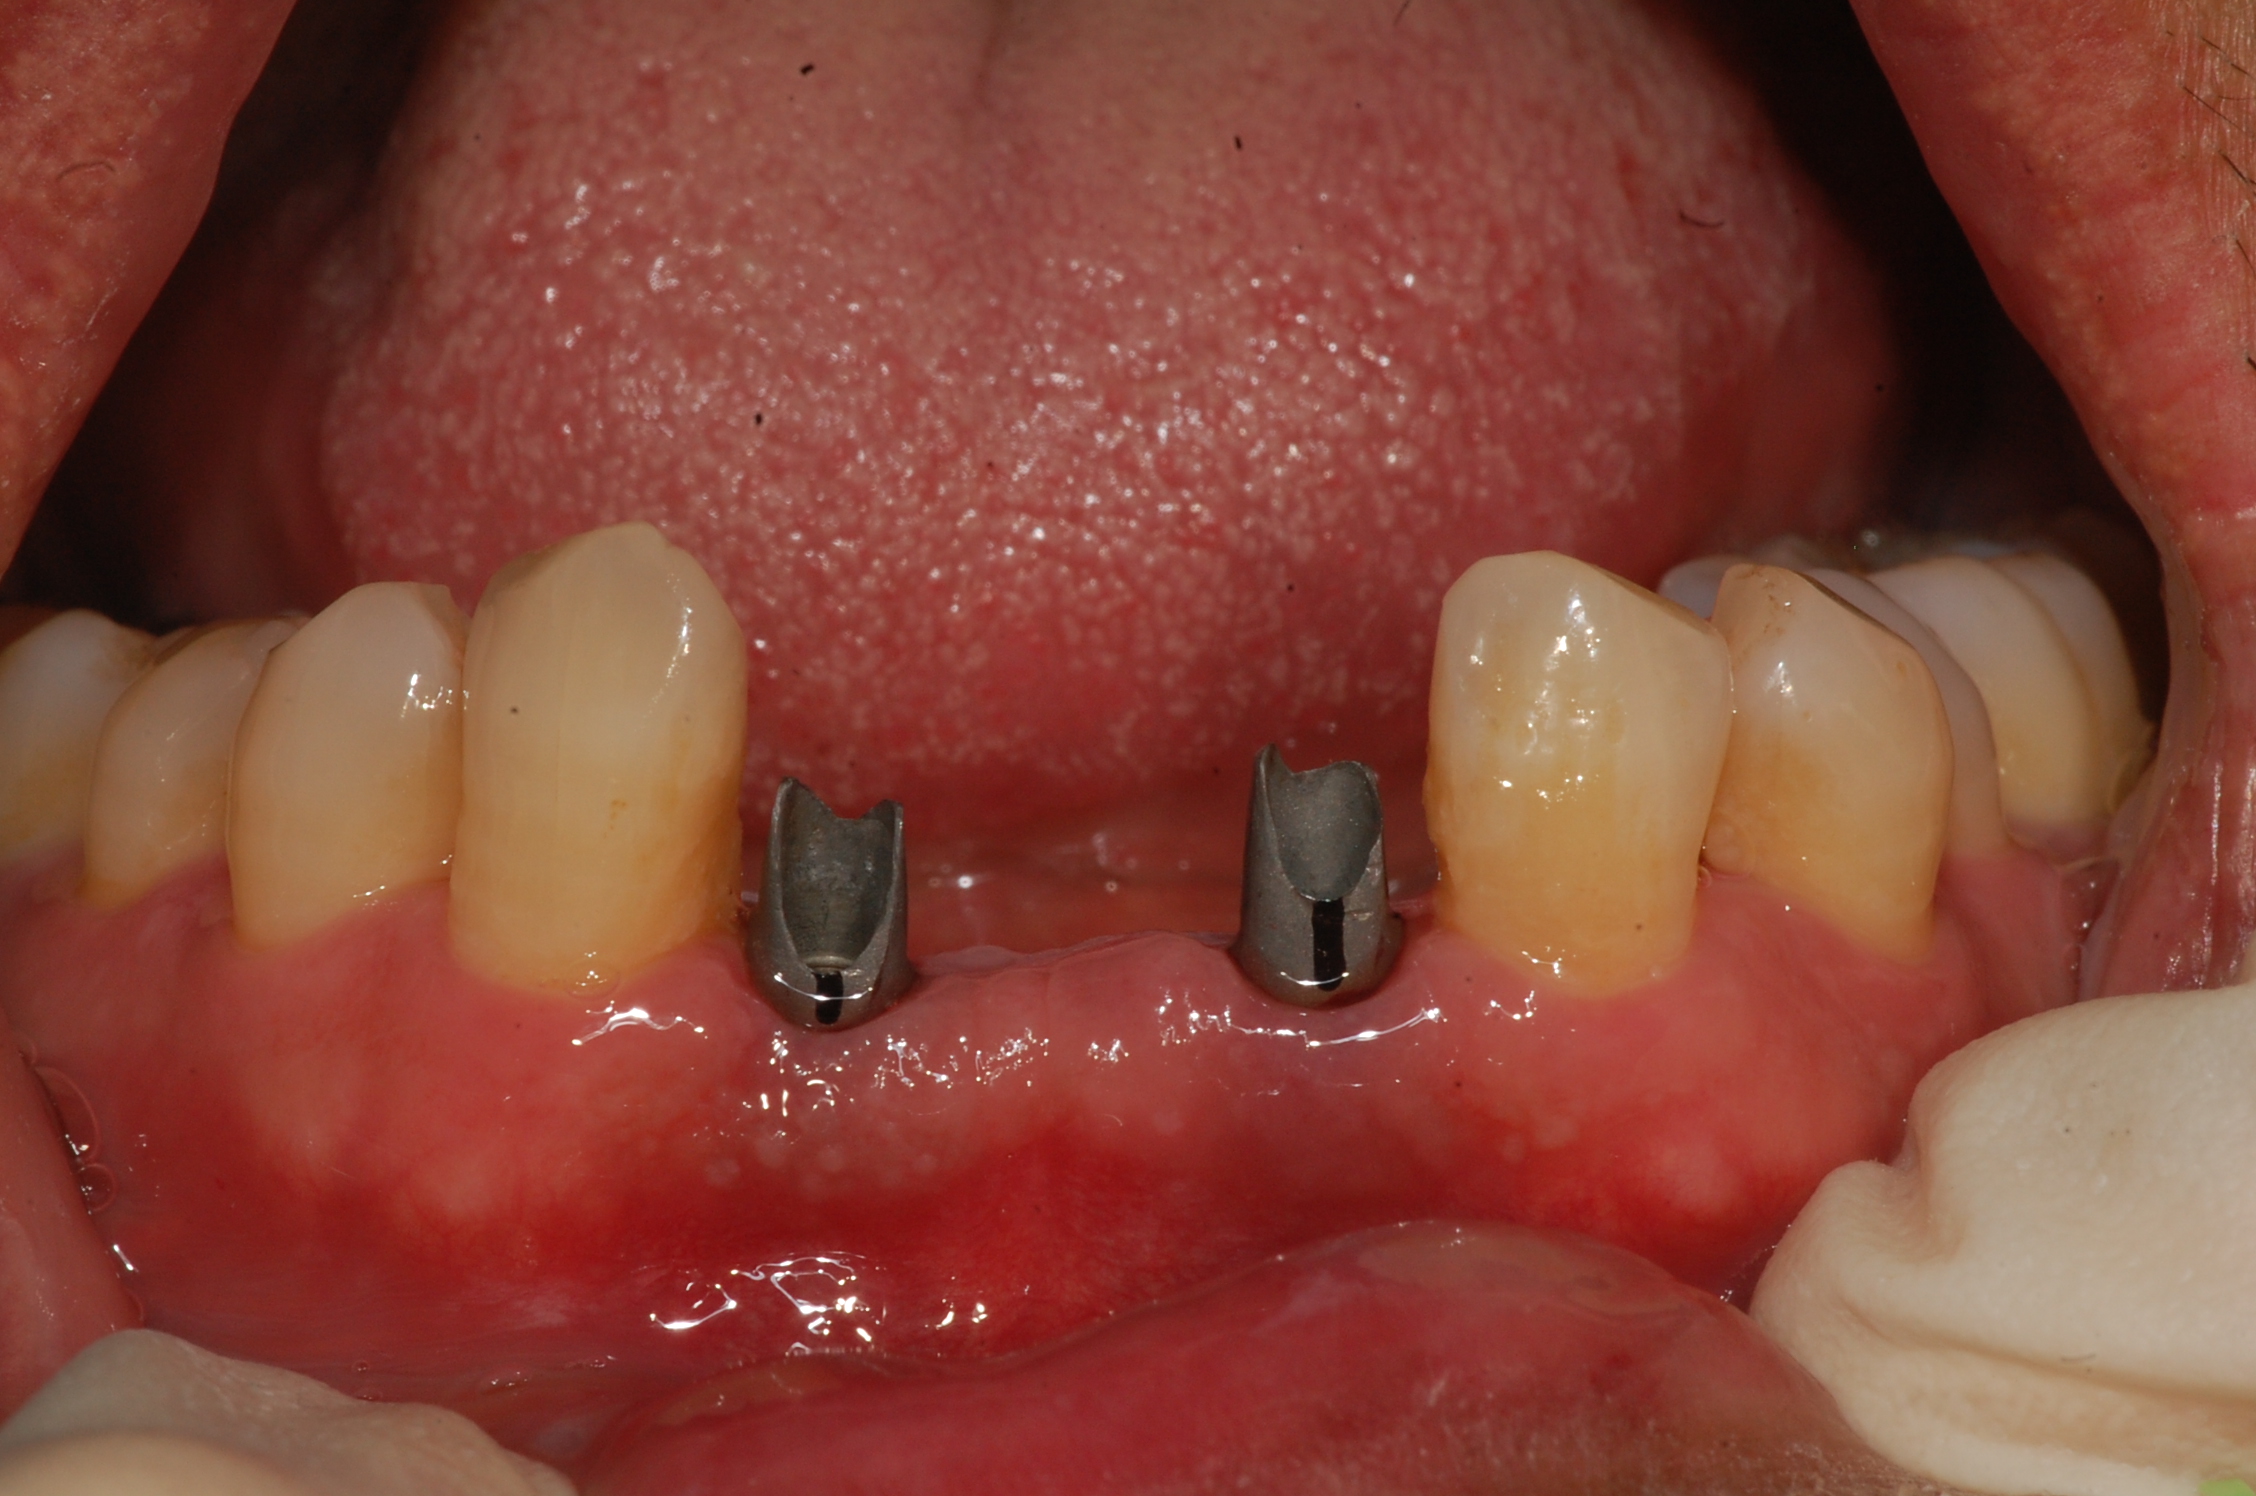

[임플란트] 제목 : 아래 앞니 임플란트

치주질환으로 발치 후 치료